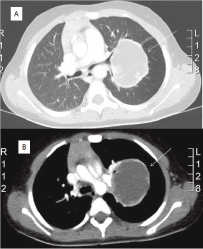

In our case, the patient was a four-year-old girl, which was unusually young when compared with the previously reported cases [1–6]. The most common CT finding of EES reported is a heterogeneous mass [1–3], but in the present case, the CT showed the EES as a cystic structure.

Figure 2: CT scan: (A) cystic tumour in the middle of left lung between the superior and the lower bronchus with maximum diameter of 10/8 cm (arrow); (B) close contact of the tumour (arrow) with the left pulmonary artery